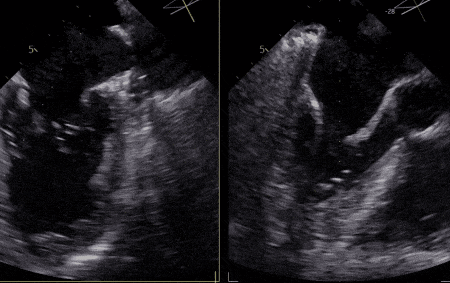

▲患者术前超声影像

患者二尖瓣3区前叶脱垂,脱垂宽度13mm,瓣口面积5.6cm2,平均跨瓣压差1.3mmHg。术前评估病人情况后决定采取策略在反流最大处植入一枚到两枚XTR或NTR,降低反流。